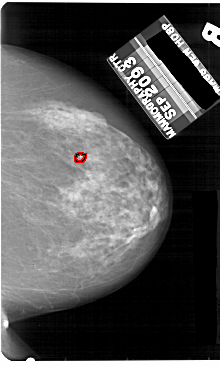

A_1859_1.RIGHT_MLO

RIGHT_MLO LINES 5491 PIXELS_PER_LINE 3616 BITS_PER_PIXEL 12 RESOLUTION 43.5 OVERLAY

FILE: A_1859_1.RIGHT_MLO.OVERLAY

TOTAL_ABNORMALITIES 1

ABNORMALITY 1

LESION_TYPE CALCIFICATION TYPE PLEOMORPHIC DISTRIBUTION CLUSTERED

ASSESSMENT 4

SUBTLETY 4

PATHOLOGY BENIGN

TOTAL_OUTLINES 1

BOUNDARY